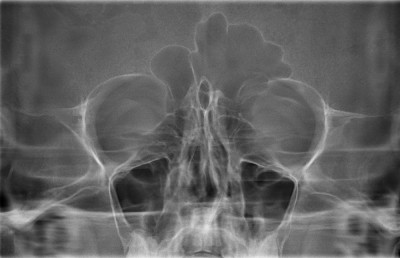

Рентгенограмма приносовых синусов.

Расшифровывая снимок пациента с синуситом, можно сразу же провести более детальную дифференциальную диагностику, согласно его локализации и распространенности.

Рентгенологическая классификация синуситов:

По локализации:

- Гайморит – локализация в гайморовых (верхнечелюстных) пазухах.

- Фронтит – патология лобных синусов.

Сфеноидит – воспаление пазухи клинообразной кости.

- Этмоидит – воспалительный процесс в синусах сосцевидного отростка.

По распространенности:

- Моносинусит – процесс протекает только в одном синусе.

- Полисинусит – в воспаление втянуты несколько пазух разных костей.

- Гемисинусит – поражение всех пазух с одной из сторон (правой или левой).

- Пансинусит – одновременное втягивание в воспалительный процесс всех околоносовых пазух.